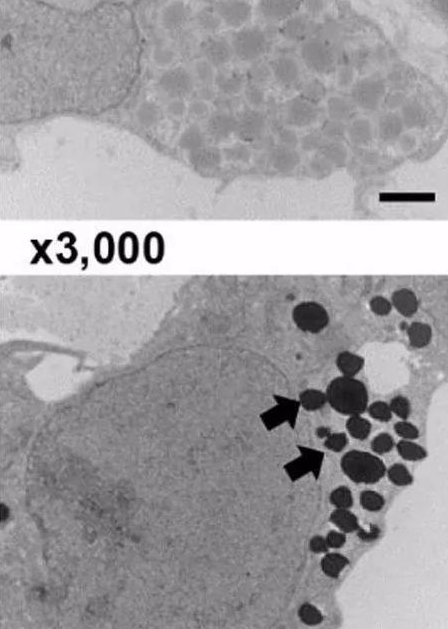

圖. 電鏡下細(xì)胞內(nèi)EPO的分泌囊泡

120.png